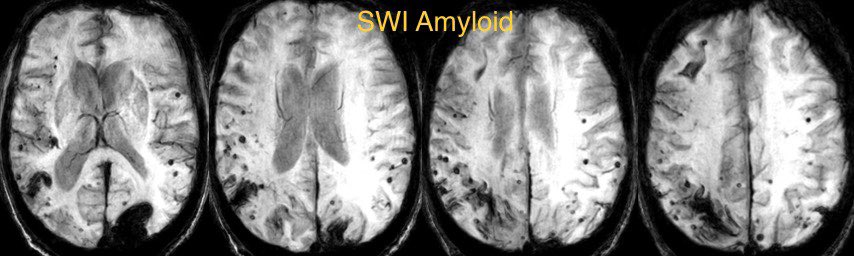

💡 Typical micro bleed pattern in cerebral amyloid angiopathy (best seen on SWI/T2*):

▶️Peripheral cortical and subcortical microhemorrhages

▶️Parietal and occipital lobes most commonly involved

▶️Tend to spare basal ganglia and brainstem

💡 May also have lobar hemorrhages, lobar lacunar infarcts, convexity subarachnoid hemorrhage, superficial siderosis, cerebral atrophy, and clinical signs of dementia